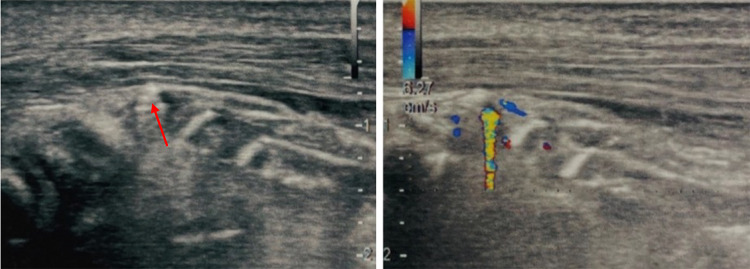

Fig. 6.

Case 6. A 27-year-old man was admitted to our hospital with discomfort in the right leg. He reported that he had hit his leg several times falling on the ground. The discomfort was very intense, and in the portion which was most painful on palpation US grayscale image showed two small hyperechoic areas that merged with the echogenicity of the surrounding subcutaneous soft tissue. In this case, CDUS showed the presence of small FBs clearly evidenced by TA

Fig. 7.

Case 7. A 55-year-old man was admitted to our hospital with pain in the palmar region of his left hand. The patient reported having had a work accident in which he injured his hand with a metal plate. Because of the material with which the patient was injured, X-ray of the hand was performed showing a radiopaque formation projecting ventrally and laterally with respect to the metacarpophalangeal joint of the second finger. For a better localization, US grayscale imaging was performed showing a tenuous hyperechoic streak below which the TA was clearly visible. Subsequently the patient underwent surgery and removal of the FB